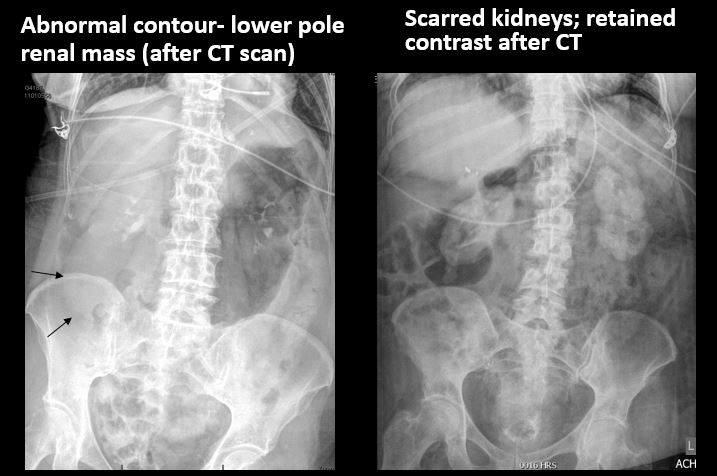

There is an abnormality of the size or contour of the right and/or left kidney. [Yes/No]

There are renal associated calcifications. [Yes/No]